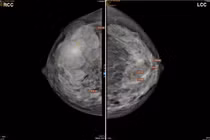

thuoc-la-1.png

Hình ảnh khối ung thư vú sưng to, lở loét trước điều trị - Ảnh BVCC

Tại thời điểm nhập viện, các bác sĩ ghi nhận khối u kích thước lớn, khoảng 6 x 8 cm, xâm nhiễm và gây lở loét da toàn bộ vùng ngực bên phải. Khối u đã dính vào cơ ngực lớn, rỉ dịch mủ, máu tanh hôi.

Thăm khám và thực hiện cận lâm sàng, các bác sĩ xác định bệnh ở giai đoạn T4B (khối u lở loét, xâm nhiễm da, dính vào thành ngực), kèm nhiều hạch nách cùng bên dính chùm (giai đoạn N2), cho thấy bệnh đã phát hiện muộn và ung thư vú đang tiến triển ở giai đoạn nặng. Điều này đòi hỏi việc can thiệp sớm và toàn diện để kiểm soát bệnh, cải thiện tiên lượng sống cho bệnh nhân.

Hiện tại, sau hai chu kỳ hóa trị, bệnh nhân đáp ứng tốt với điều trị, kích thước khối u giảm còn khoảng 4 x 5 cm, mức độ xâm lấn cơ ngực giảm rõ rệt, cải thiện khoảng 50% so với trước điều trị.